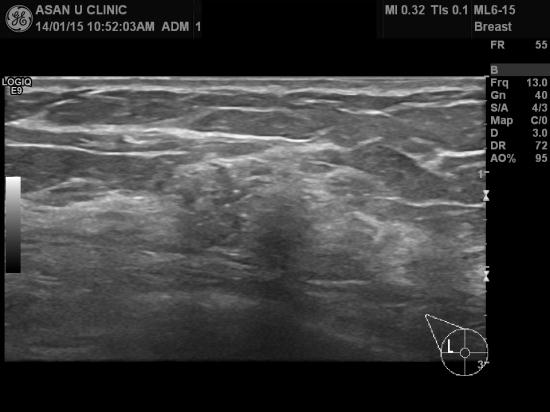

아산유외과 개원 후 59번째 유방암 진단.

건강검진상 이상소견이 있어 조직검사 위해 의뢰된

53세 여성분입니다.

군집을 이루는 미세석회화가 유방촬영에 보였고

그부위 초음파를 통한 중심핵생검으로 우측유방에 침윤성 유관암이 진단되었습니다.

환자분께선 1달밖에 모유수유를 못해서 생긴건지 의아해하십니다.

이년전 건강검진때는 정상이었다고요......

건강검진이 유방암의 발생을 예방하는 것이 아니라

조기에 진단할 수 있도록 도와주는 것 밖에는 최선의 역할이 없네요.